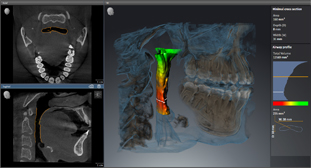

Анализ дыхательных путей с SICAT Air

Специальная функция привлечёт в вашу клинику людей с проблемами дыхательной системы.

Интегрированная имплантология с GALILEOS Implant

Все манипуляции, связанные с операциями имплантологического плана эффективны и безопасны. Для того чтобы наиболее оптимальным способом спланировать лечение, есть возможность совмещения цифровых слепков и рентгеновских изображений и объединения данных SIDEXIS 4 и CEREC 44.

Благодаря интегрированию в рабочий процесс Sirona специалисты клиники имеют возможность составлять различные схемы лечения, в том числе включая комплексную имплантологию с использованием ПО GALILEOS Implant и хирургических шаблонов (например, шаблонов CEREC 2), а также диагностику и терапию дыхательных путей с помощью SICAT AIR и SICAT OPTISLEEP.